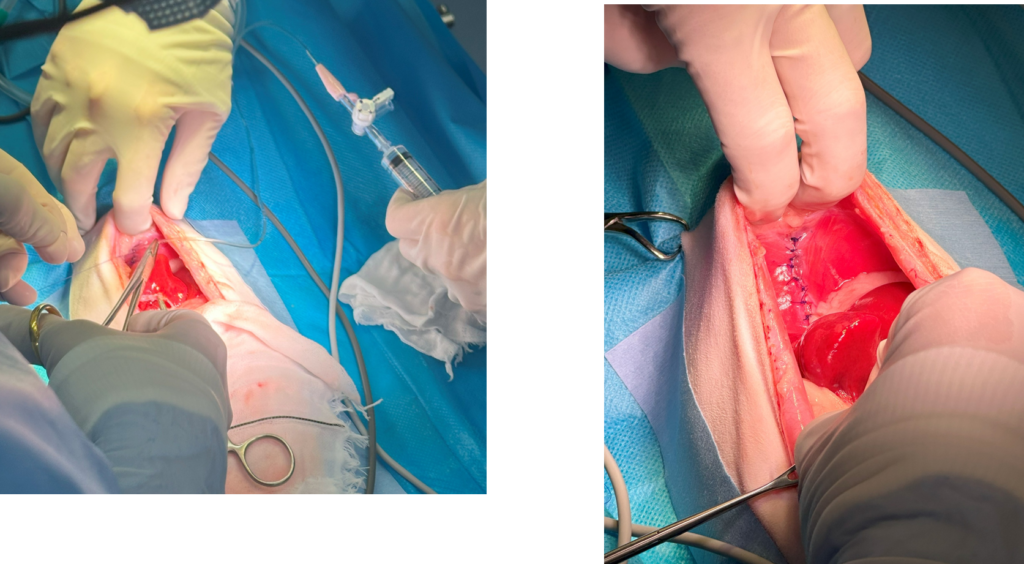

手術の様子

緑の点線が囲っている場所が横隔膜にあいた穴から肝臓が入り込んでいるところです。鉗子を使って周囲の膜をはがしていきます。

ヘルニア孔をみつけて胸の中に入り込んでいる肝臓を引き出します。

肝臓を戻したらヘルニア孔を縫合して閉じていきます。

孔を完全に閉じる前にチューブを挿入して胸腔内の空気をできるだけ抜去します。

完全に孔を閉じます。あとはお腹の皮膚を閉じて手術終了です。